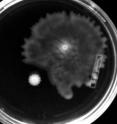

The researchers didn't set out with the goal to evolve hyperswarmers, but they did passage Pseudomonas aeruginosa on special plates over a period of days. On those plates, bacteria that could spread out had an advantage in harvesting nutrients from the surface, and within a matter of days, some of those bacteria started hyperswarming.

Investigation of the bacteria showed that P. aeruginosa gained its hyperswarming ability through a single point mutation in a flagellar synthesis regulator (FleN). As a result, the bacteria, which usually have one single flagellum, were locked into a multi-flagellated state. They became better at moving around to cover a surface, but much worse at forming densely packed, surface-attached biofilm communities. All told, the researchers saw this new ability independently arise 20 times.